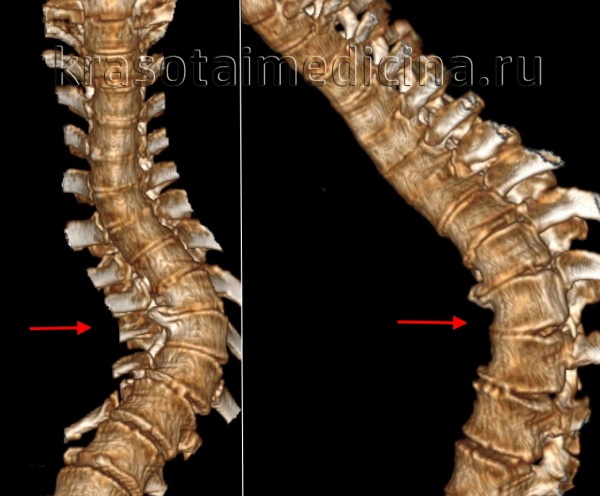

очень важно выявить кифасколиоз у детей в начальной степени развития и своевременно начать его лечение. Диагностируют кифосколиоз по снимкам рентген обследования, МРТ (магнитно-резонансной томографии) и компьютерной томографии. Снимки желательно делать в двух проекциях: спереди и сбоку. Снимки МРТ на сегодняшний день считаются одним из самых точных диагностических методов заболеваний позвоночника.

Возможен как «чистый» кифоз, при котором позвоночник искривляется только в передне-заднем направлении, так и кифосколиоз, сопровождающийся искривлением в передне-заднем и боковом направлениях. Вершина кифотического искривления может располагаться на любом уровне – от шейно-грудного до поясничного отдела позвоночника. Кифоз при этом заболевании часто носит прогрессирующий характер.

В качестве дополнительных методов исследования используется рентгенография (обзорные и прицельные снимки в различных проекциях), КТ, МРТ. Может назначаться рентгенконтрастное исследование позвоночного канала. Обязательно проводится неврологическое обследование. Консервативное лечение врожденного кифоза малоэффективно. Рекомендуется оперативное вмешательство в детском возрасте для устранения патологического кифоза, стабилизации позвоночника и предотвращения его дальнейшей деформации.

Кифосколиоз – это комбинированная деформация позвоночника, представляющая собой сочетание сколиоза (бокового изгиба) и кифоза (сутулости, избыточного изгиба в переднезаднем направлении). Может быть врожденным или приобретенным, проявляется видимой деформацией и болями в спине. Из-за вторичного изменения формы грудной клетки и нарушения функций расположенных в ней органов возможна одышка и нарушения сердечной деятельности. Диагноз выставляется на основании внешних признаков, данных рентгенографии, МРТ и КТ. Лечение кифосколиоза обычно консервативное, при выраженном искривлении может возникнуть необходимость в операции.

В зависимости от выраженности деформации выделяют 4 степени кифосколиоза:

- 1 степень кифосколиоза – угол искривления позвоночника в переднезаднем направлении 45-55 градусов. Отмечается незначительное боковое смещение и скручивание (ротация) позвонков.

- 2 степень кифосколиоза – угол искривления позвоночного столба в переднезаднем направлении 55-65 градусов. Выявляется заметное скручивание и боковое смещение.

- 3 степень кифосколиоза – угол искривления позвоночника в переднезаднем направлении 65-75 градусов. Формируется позвоночный горб, отмечается видимая деформация грудной клетки.

- 4 степень кифосколиоза – угол искривления позвоночного столба в переднезаднем направлении более 75 градусов. Как и в предыдущем случае искривление сопровождается образованием позвоночного горба и деформацией грудной клетки.